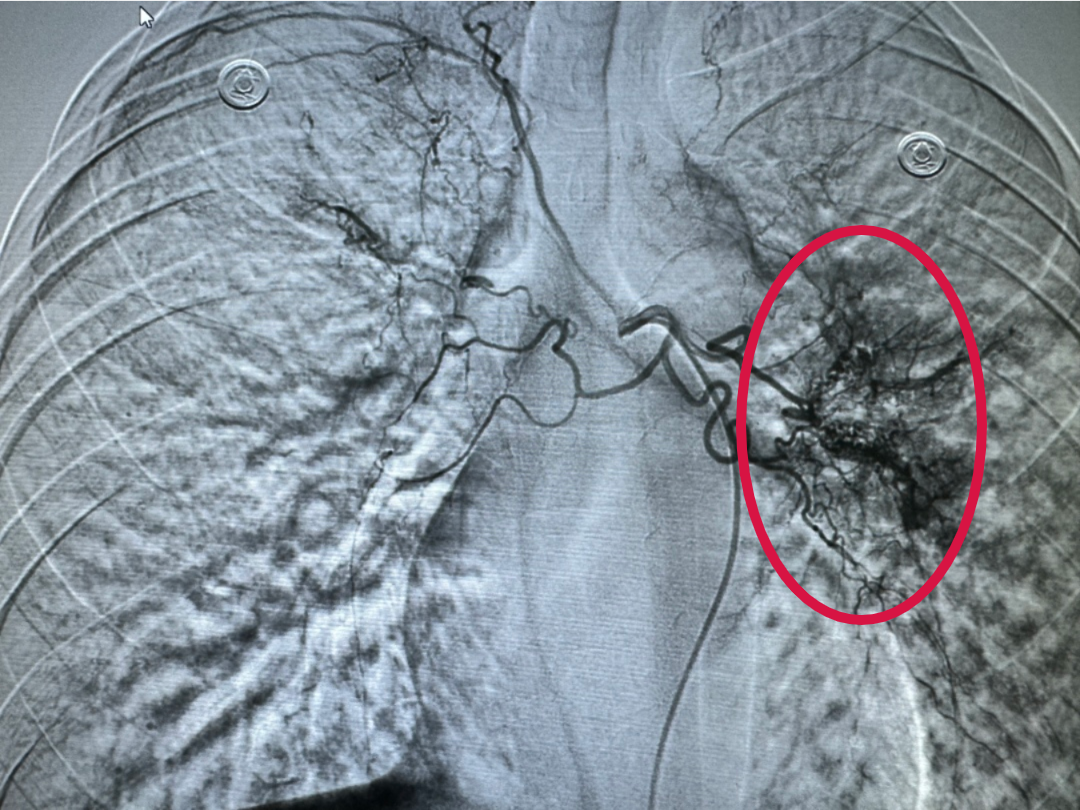

造影下,可见出血位置,出血量大

当天凌晨1点,在病房休息的张某突发大咯血,咯血量已超300ML,特别危险的是患者在咯血中极易造成气管堵塞,一旦发生意外,患者窒息死亡。呼吸内科黎晓萍主任接到科室急救电话后立即赶到病房,病情危急,做完评估,见过大风大浪的她当机立断,马上联系肿瘤科郑立刚主任前来紧急会诊,会诊后,决定在大C臂下为患者做经导管双侧支气管动脉造影术+动脉栓塞术,紧急为患者封堵出血血管,让其停止咯血,后立即把患者送入介入室开展介入急诊手术。手术成功把出血血管封堵缺口,患者也停止咯血,这时,所有人才放下了悬着的心。

经导管支气管动脉栓塞止血术是一项高难度的手术,需要医生精确地定位出血口,在极小的、错综复杂的血管里,巧妙的把材料封堵住血管出血口,才能确保手术的成功。在这次手术中,多学科的医务人员紧密配合,各展所长,充分发挥各自的专业技能,成功抢救了患者生命。